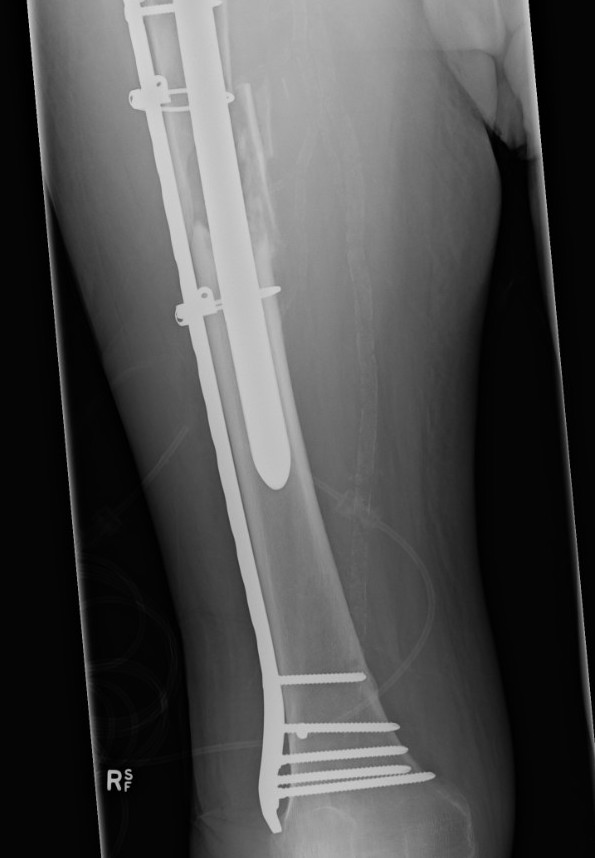

Type C: Fracture distal to tip of stem

Management

ORIF Locking cable plate +/- cortical strut allograft

- overlap femoral implant

- to distal femur